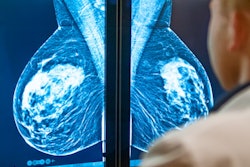

The effect of breast screening is stronger and longer-lasting in women who are 65 and old, but it remains highly relevant for younger women, according to new data from England published on 23 November in the British Journal of Cancer (BJC).

The National Health Service (NHS) breast screening program case-control study of over 23,000 women showed a 37% reduction in mortality for women screened at least once, corresponding to approximately nine breast cancer deaths prevented between the age of 55 and 79 for every 1,000 women attending screening between the ages of 50 and 69.

Measures of the benefit of screening are largely influenced by the consequent reduction in mortality from symptomatic cancers, noted first author Roberta Maroni, a statistician at the Wolfson Institute of Preventive Medicine, Queen Mary University of London. Screen-detected cancers -- defined as the ones diagnosed within three months of a screen -- represent a larger proportion of the cancer-related deaths in the immediate period after a screen, despite being less fatal overall. The spike in excess mortality in the figure below illustrates this point.

The duration of the benefit of attending screening appears to be greater in older women (OR = odds ratio). All figures courtesy of Prof. Stephen Duffy and the BJC.Overall, the England-wide study showed that, despite major improvements in diagnostic techniques and treatments, mammography screening continues to play an important role in lowering the risk of dying from breast cancer.